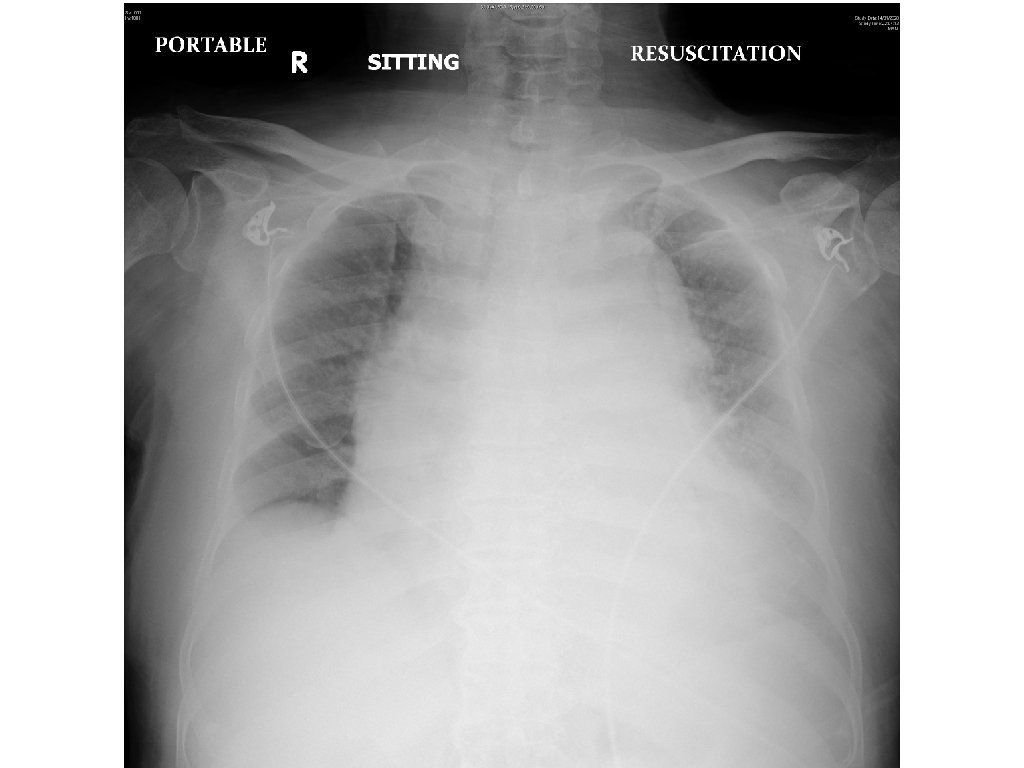

Case 3 • A 90 year-old man presented with sudden onset of back and chest pain. • His BP was 87/58, pulse 68/min. • A CXR was done.

Case 3 - Questions 1. Name three CXR abnormalities. 2. Name two useful bedside investigations and what to look for. 3. Name two most significant CT findings? 4. What is the diagnosis?